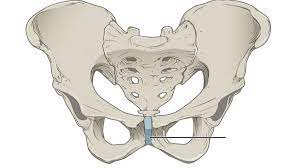

¿Cuáles son las articulaciones cartilaginosas?

Las articulaciones cartilaginosas son un tipo de articulación en la cual las superficies articulares de los huesos están unidas por formaciones de cartílago hialino (sincondrosis) o fibrocartílago. Un ejemplo común…